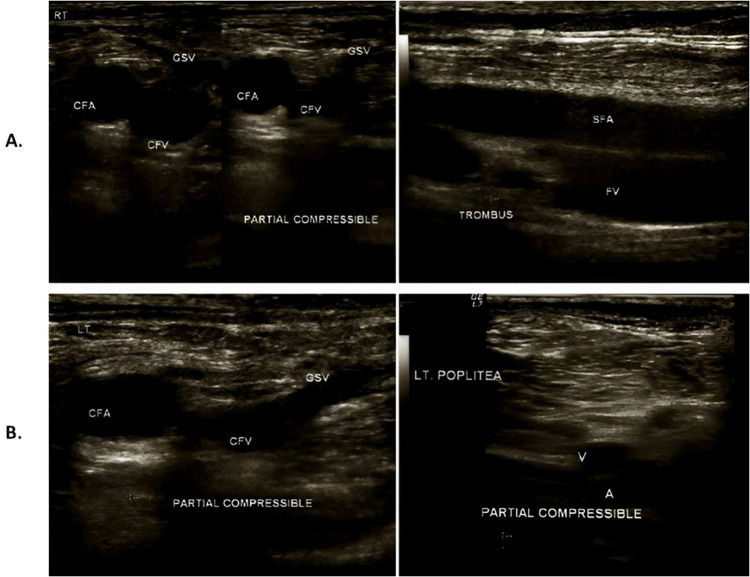

Gallbladder adenocarcinoma has a high mortality rate, with approximately 1.7% cancer-related deaths worldwide. Cancer-associated thrombosis (CAT), including deep vein thrombosis (DVT), can significantly increase the risk of mortality within cancer patients, especially in pancreatic, brain, and intra-abdominal cancers, as well as in advanced and metastatic cancers. In this case report, there was a 45-year-old male patient diagnosed with advanced gallbladder adenocarcinoma UICC stage IVB with a TNM stage of T2b, N0, M1 with liver metastases who experienced pain and swelling in both lower limbs after undergoing a VI-A cycle of chemotherapy with gemcitabine capecitabine. The risk of thrombosis was calculated using the modified Khorana-Vienna CAT scores, which increased during every chemotherapy session. In this case, the Khorana-Vienna CAT score was calculated during two latest cycle of chemotherapy that somewhat considered delayed as the patient had already shown hypercoagulopathy symptoms and developed a poorer prognosis. Early CAT scoring, ideally before starting chemotherapy session, potentially improves thrombosis prognosis. The patient's condition improved after administration of antithrombotic agents. Chemotherapy agents and other factors, including the cancer site and presence of metastatic cancer, influence the risk of CAT. Risk predictor scores are required to assess the risk of CAT and benefits of prophylactic treatment. Prophylactic therapy can be initiated in patients with high-risk CAT, calculated using the modified Khorana and Vienna CAT scores, to prevent thrombosis and improve patient outcomes.